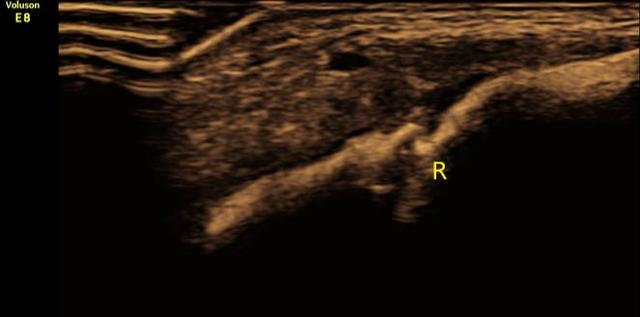

尽管如此,还是有很多家长担心X光的放射性,在选择拍X光片时常常忧心忡忡,因而可以选择超声诊断!超声检查作为最常用且最安全的一种临床诊断方法,它不仅无创、无痛、方便快捷又准确,还可以定期随访骨折的愈合情况。

出生后的一大段时间里,可能医生或者家属都还蒙在鼓里,不知道宝宝发生了锁骨骨折。直到有一天,你注意到宝宝一侧上肢不动或少动;给宝宝穿衣服,洗澡或者牵拉宝宝一侧上肢时哭泣,或者发现两边的锁骨位置不一致,或者按压锁骨局部宝宝哭闹挣扎等情况,那肯定是要高度怀疑发生锁骨骨折了。新生儿锁骨骨折的确诊方法主要有两种:X线和超声。